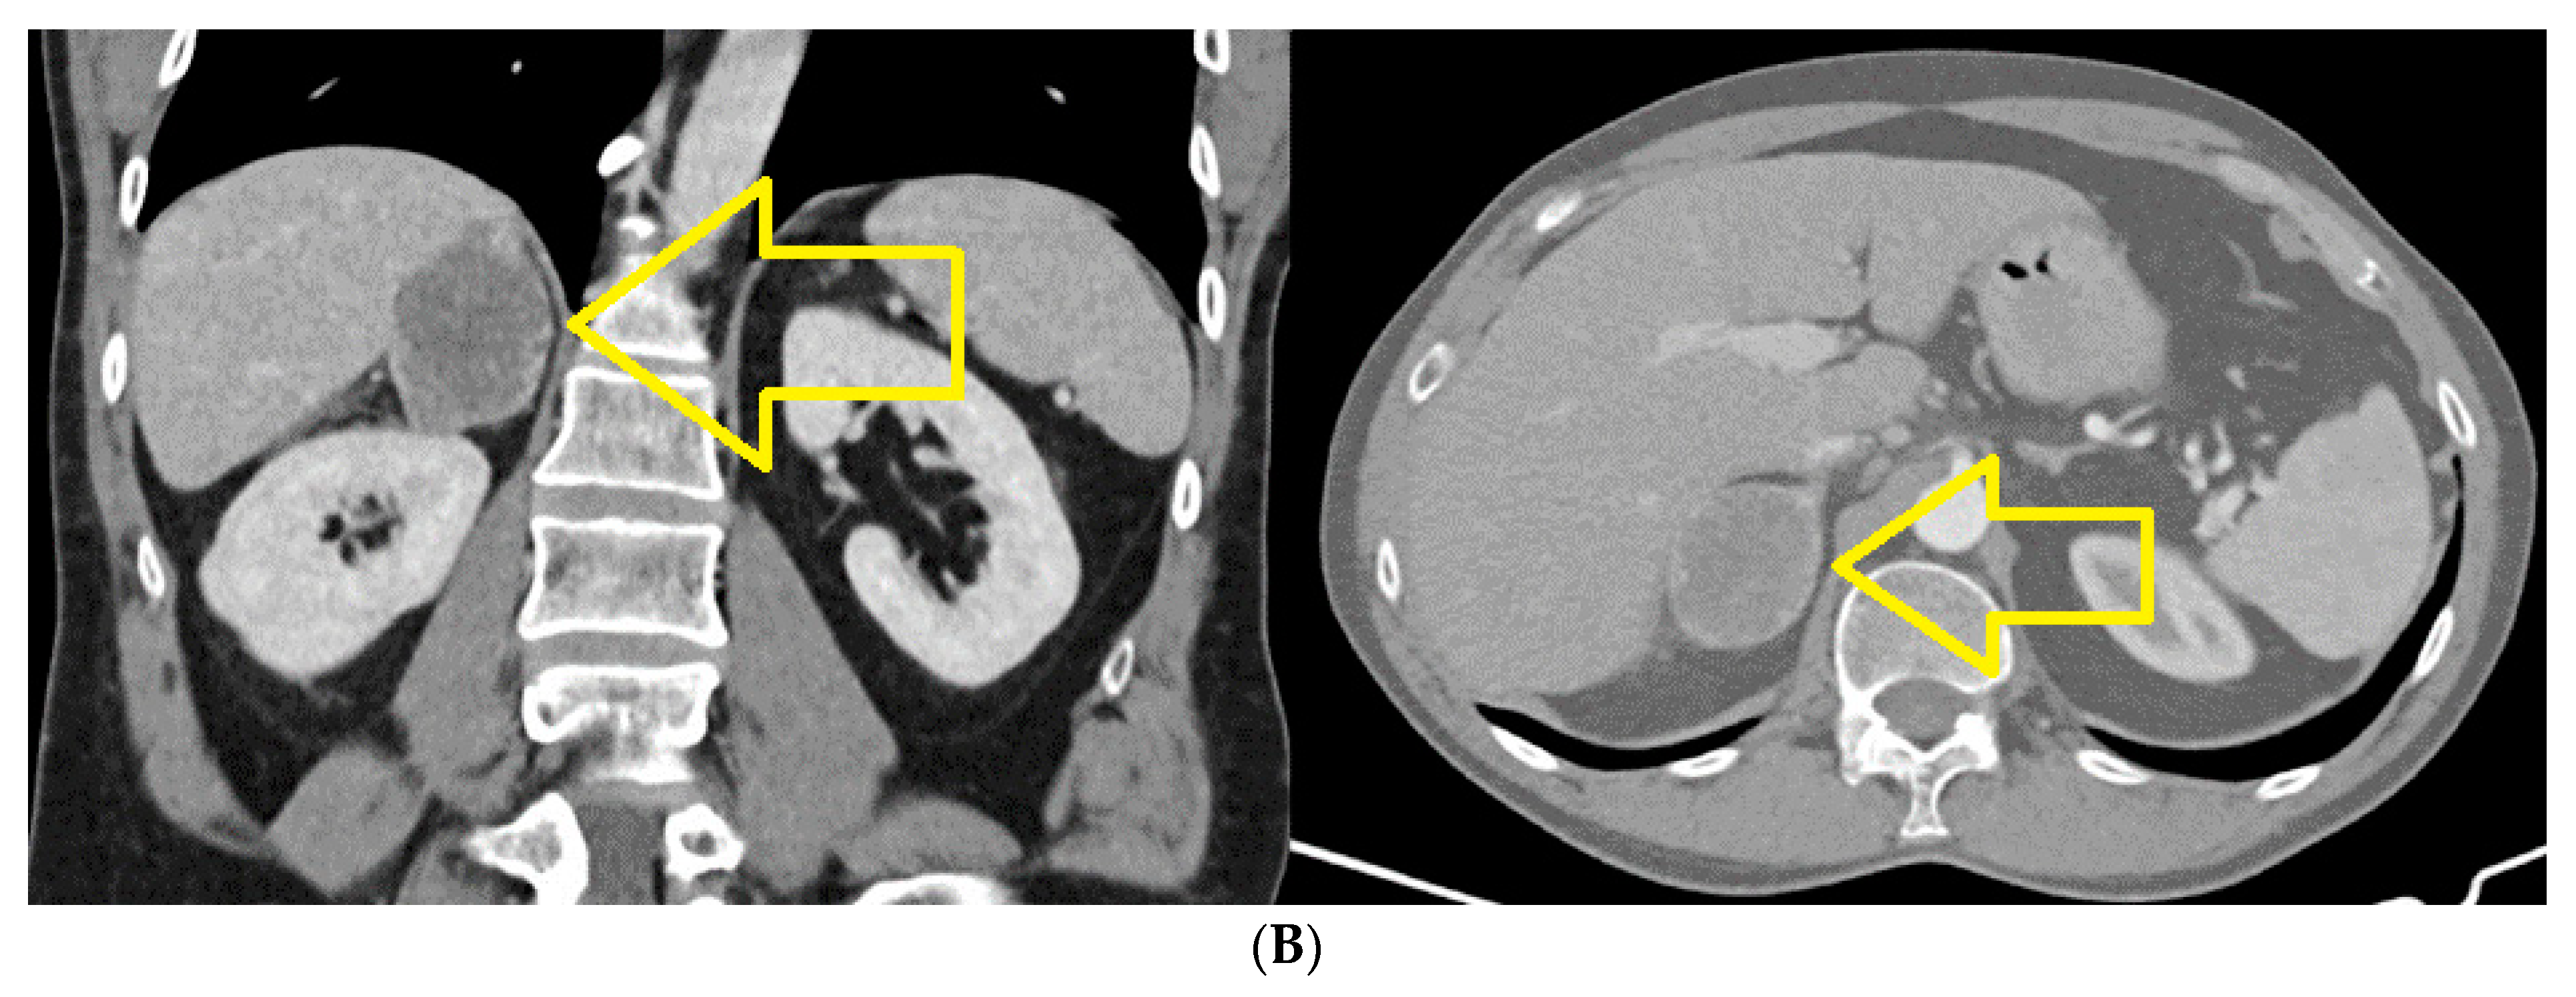

2. Case Report